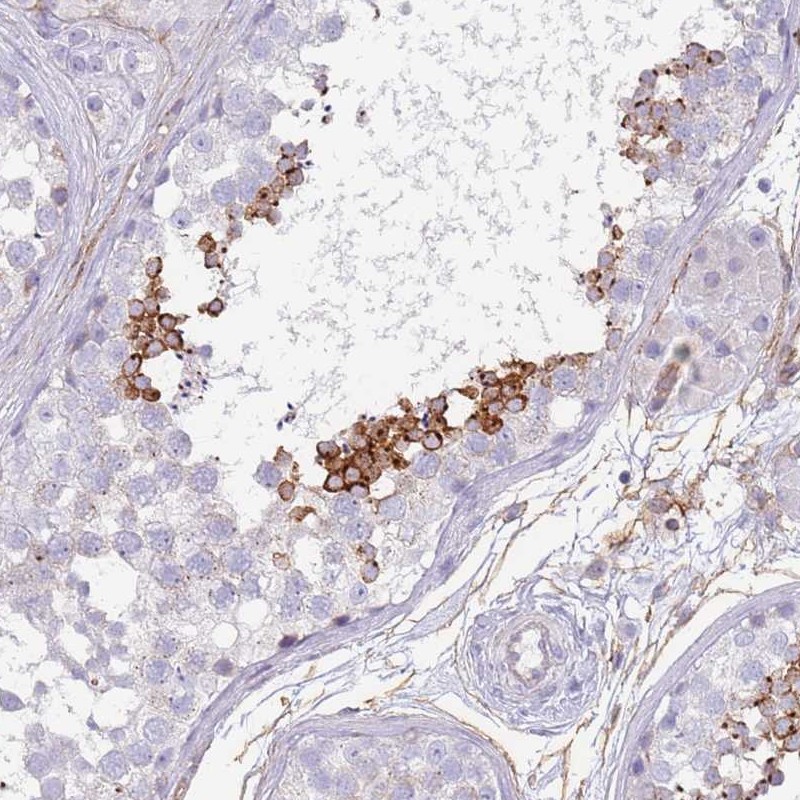

Immunohistochemical staining of human testis shows strong cytoplasmic positivity in a subset of cells in seminiferous ducts.